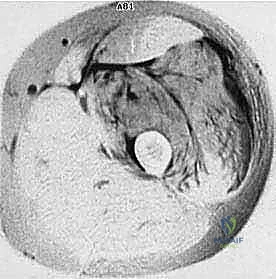

المرحلة الأولى: استئصال الورم (Resection)

يتم فتح الجلد والأنسجة بعناية فائقة. التحدي الأكبر هنا هو فصل الورم عن الأوعية الدموية والأعصاب الرئيسية المغذية للطرف. يستخدم الدكتور هطيف تقنيات الجراحة الميكروسكوبية لضمان سلامة هذه الهياكل الحيوية، مما يحافظ على حيوية الطرف وحركته.

- الجراحة الميكروسكوبية (Microsurgery): لخياطة الأوعية الدموية والأعصاب الدقيقة التي لا تُرى بالعين المجردة، مما يضمن تدفق الدم للطرف بعد الاستئصال الواسع.